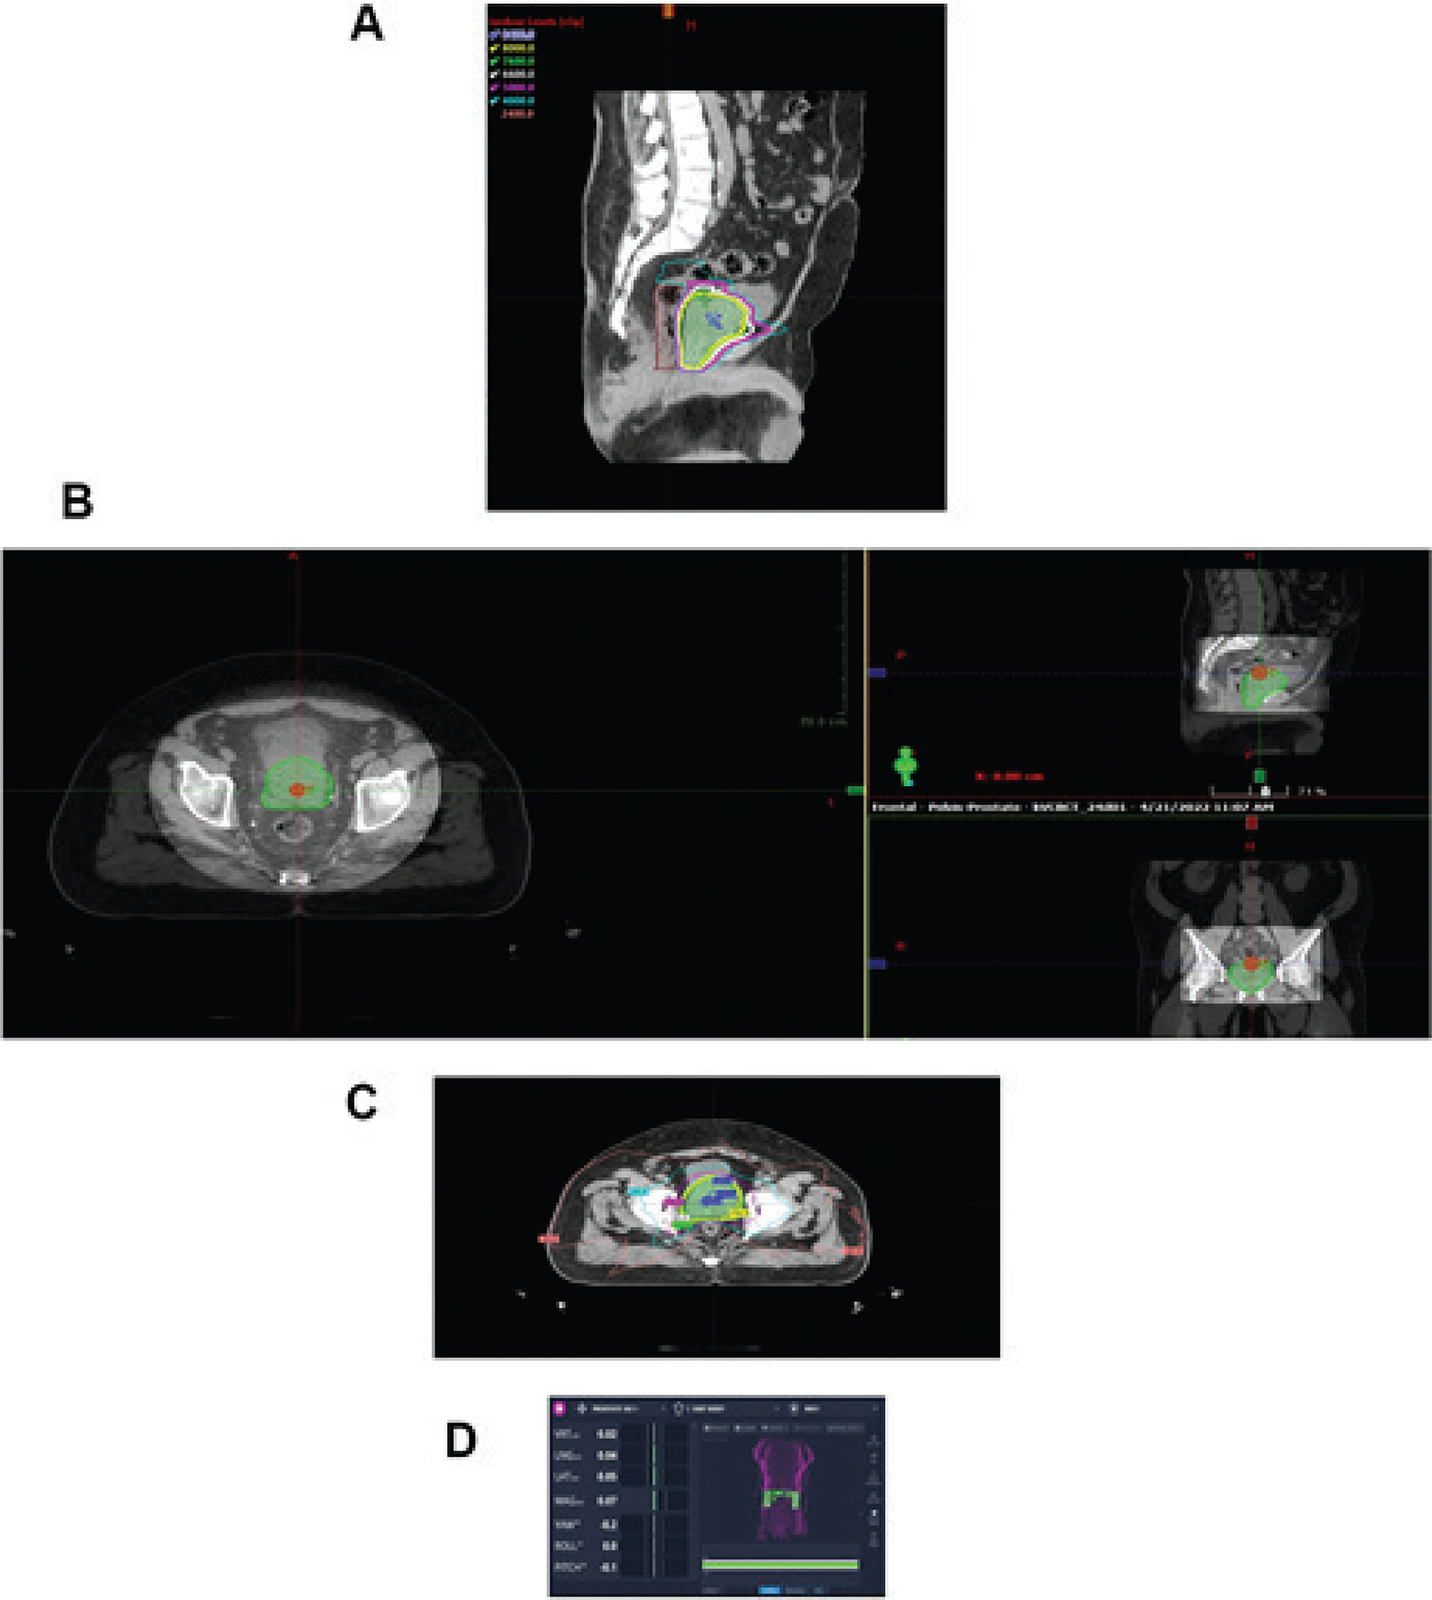

The advances in external beam radiation therapy treatment planning and delivery have positioned radiation therapy very well in the care of patients with prostate cancer. Image guidance secures and confirms the significant impact of intensity modulation on patient care. Because of the security of daily treatment execution, radiation oncologists have been able to adjust daily treatment dose to levels securing optimal outcome (3, 712). The process improvements in technology have permitted investigators to compress both daily and total treatment time without accelerated risk for normal tissue injury (3, 711, 13). Hypofractionation protocols decreasing the duration of treatment with increased daily dose are maturing and many investigators in the radiation oncology community consider compressed treatment programs moving towards the standard of care in patients with normal and near normal prostate anatomy and genitourinary function (811, 14, 15). Brachytherapy as monotherapy remains an outstanding therapy option for patients with low and early intermediate risk disease (3, 1619). Modern real time image guidance in the development and execution of the plan has made brachytherapy an outstanding treatment option. Brachytherapy with external therapy provides excellent outcomes in patients with less favorable intermediate-risk disease and high-risk disease when anatomically appropriate (Figure 2).

Fig 2

Figure 2. Permanent seed brachytherapy. This image shows the application of permanent seed brachytherapy in a high stage patient with the radiation dosimetry superimposed on the image courtesy of the Department of Radiation Oncology, UMass Chan Medical School and UMass Memorial Health.